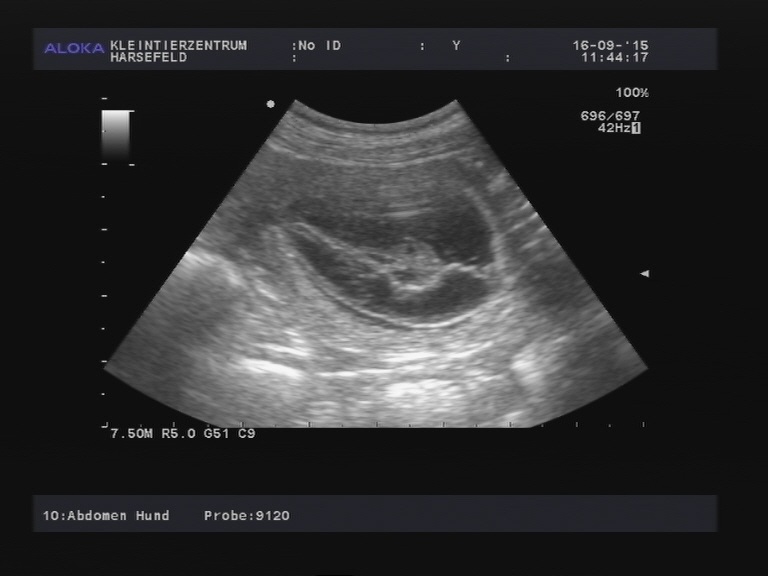

+++ Prada’s Geburts-Live-Ticker +++ 19.10.2015 - Die Eröffnungswehen sind dezent im Gange und die Entleerungsphase läuft seit heute nachmittag...